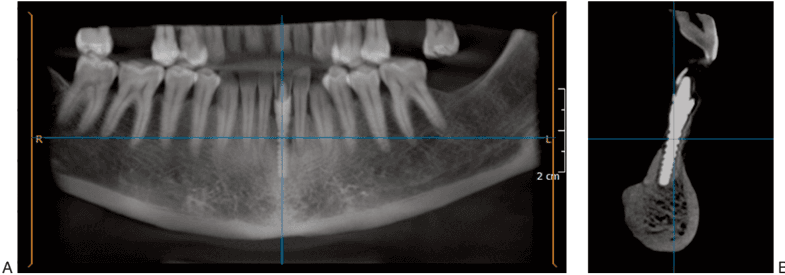

Together with our scientists, these academic institutions carry out advanced studies to understand and optimize the therapeutic potential of microfragmented adipose tissue (MFAT), with a focus on tissue regeneration, angiogenesis, anti-inflammatory and antibacterial properties.

Thanks to an in-depth analysis of the secretome – the set of biomolecules released by MFAT – we explore the biological mechanisms that regulate cell growth, tissue repair and intercellular communication.

These studies, published in prestigious scientific journals (Stem Cell Int. 2019, Vasc Cell 2016, Br J Anaesth. 2018), not only expand scientific knowledge, but have a direct impact on clinical protocols adopted by Image Milano, ensuring advanced treatments based on the latest scientific evidence.